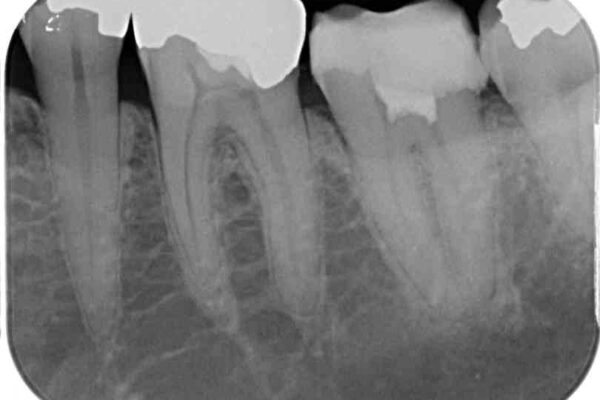

診査をしたところ、神経組織に影響を及ぼすような大きな虫歯があることが分かりました。

虫歯が歯髄腔(神経の部屋)に達している可能性が非常に高かったため、炎症を起こしている神経組織を部分的に切除し、歯根部分の神経組織を保存する治療法が望ましいと考えられました。

治療前

• 治療をしても違和感の続く奥歯 神経を極力残した虫歯治療 治療前画像